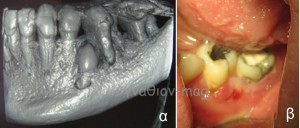

Η τελευταία περίπτωση είχε προσέλθει για συρίγγιο στην περιοχή, που οφειλόταν στον #36 (Εικόνα 3).